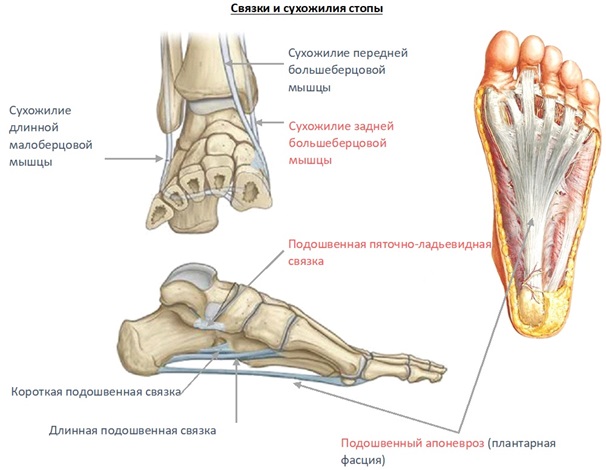

Анатомия суставов Шапарова и Лисфранка: фото и информация